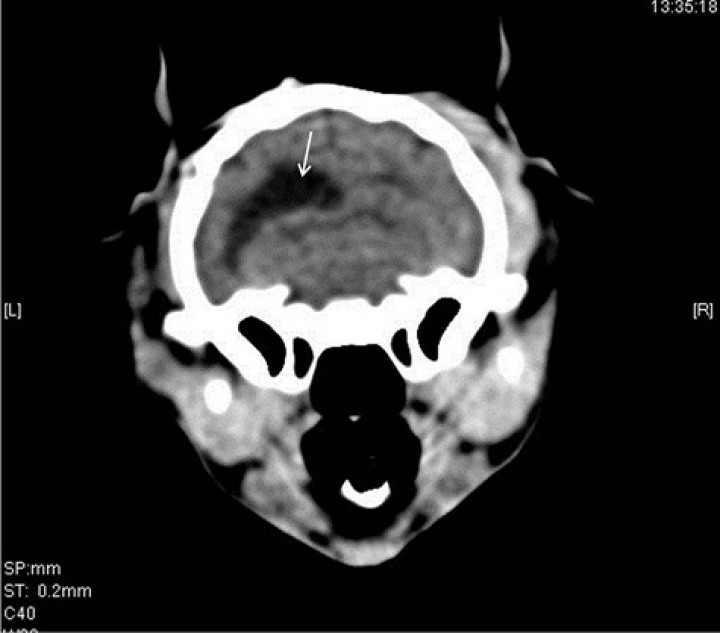

<p>TAC de revisión. Cortes transversales en algoritmo de hueso del TAC de revisión, adquirido en algoritmo de tejido blando y hueso con un grosor de 2 mm. (<strong>A</strong>) Se observa una fractura simple y deprimida en la parte temporal del hueso frontal izquierdo (flecha blanca), desplazamiento de la fosa etmoidal en su unión con el hueso frontal del lado derecho (flecha amarilla), desplazamiento del meato etmoidal y preesfenoides (flecha negra), y fractura simple de la lámina perpendicular derecha del hueso palatino (flecha azul). Además, se aprecia una lesión redonda de bordes bien definidos, hipoatenuante e intracraneal justo en la fractura de la parte temporal del hueso frontal izquierdo (flecha sólida), así como enfisema subcutáneo sobre dicho hueso (asterisco). (<strong>B</strong>) Corte a la altura de las bullas timpánicas en el que se observan dos lesiones intracraneales (con sospecha de ser intraventriculares), redondas, de bordes bien definidos e hipoatenuantes (flechas), con contenido de densidad aire (entre 976 y 1000,05 HU). Además, se observa enfisema subcutáneo a nivel temporal y parietal en el lado derecho (asteriscos).</p>

TAC de revisión. Cortes transversales en algoritmo de hueso del TAC de revisión, adquirido en algoritmo de tejido blando y hueso con un grosor de 2 mm. (A) Se observa una fractura simple y deprimida en la parte temporal del hueso frontal izquierdo (flecha blanca), desplazamiento de la fosa etmoidal en su unión con el hueso frontal del lado derecho (flecha amarilla), desplazamiento del meato etmoidal y preesfenoides (flecha negra), y fractura simple de la lámina perpendicular derecha del hueso palatino (flecha azul). Además, se aprecia una lesión redonda de bordes bien definidos, hipoatenuante e intracraneal justo en la fractura de la parte temporal del hueso frontal izquierdo (flecha sólida), así como enfisema subcutáneo sobre dicho hueso (asterisco). (B) Corte a la altura de las bullas timpánicas en el que se observan dos lesiones intracraneales (con sospecha de ser intraventriculares), redondas, de bordes bien definidos e hipoatenuantes (flechas), con contenido de densidad aire (entre 976 y 1000,05 HU). Además, se observa enfisema subcutáneo a nivel temporal y parietal en el lado derecho (asteriscos).